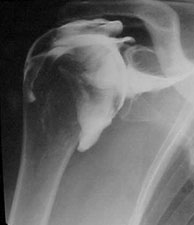

Arthroscanner : cet examen consiste à injecter un produit de contraste (visible sur les radiographies) dans une articulation. Il est couplé au scanner. L’utilisation de coupes fines avec le scanner permet une étude fine de l’articulation et des cartilages dans certaines indications (essentiellement épaule, genou, hanche, cheville).